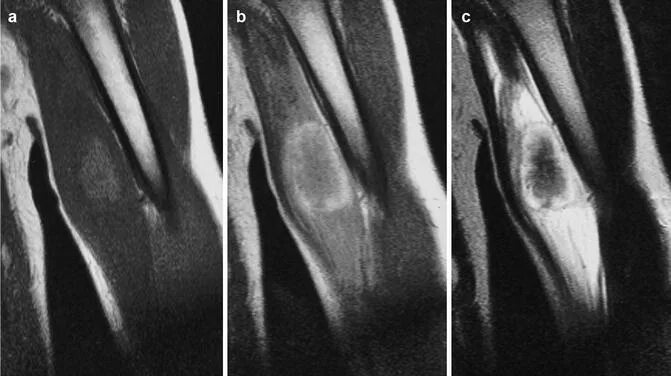

Оссифицированный миозит